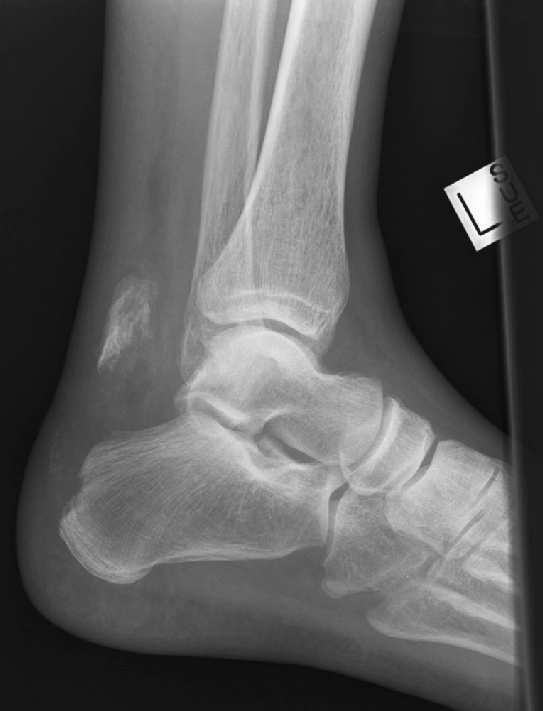

Gãy cổ xương sên (Talar neck fracture)

16/03/2026

Gãy mỏm bên xương sên (Lateral talar process fracture)

Gãy mỏm sau xương sên (Posterior talar process fracture)

Gãy xương gót (Calcaneal fracture)